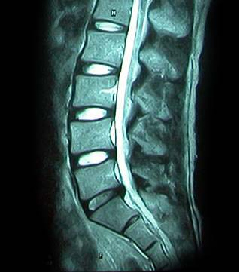

• 척추 방사선 사진1

64세 여자환자는 2개월 전부터 요통과 다리 바깥쪽과 발등, 종아리 뒤쪽으로 저린 감각이 심해져서 개인병원에 들러 평가 및 물리치료를 받았으나 별다른 호전이 없고, 1주일 전부터는 허리를 숙이거나 물건을 들 때, 오래 걸을 때 통증이 더 심해져서 본원을 방문하였다. 12년전 집안일을 심하게 하고 난 후부터 간헐적인 요통을 발생하였으며, 별다른 치료 없이 지냈으며, 4년전 무거운 물건 들고 난 후 심하게 요통과 둔부의 통증까지 발생하여 MRI 촬영상 L1-2, L3-4-5, L5-S1 HNP와 Lt. L4 & both L5 nerve compression, Lt. S1 nerve compression 진단받고 Epidural steroid injection을 받고 통증 경감되었고, 간헐적으로 통증이 발생하였으나 별다른 치료 없이 헬스클럽에서 지속적인 운동으로 관리하였다.